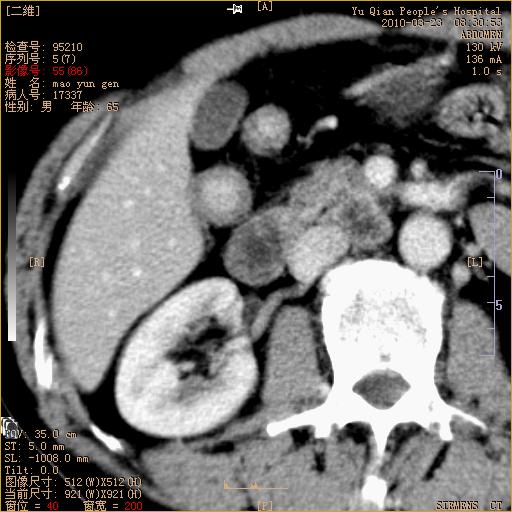

标题: CT25266:消瘦月余,前来肝部检查,请看看肠腔 [打印本页]

标题: CT25266:消瘦月余,前来肝部检查,请看看肠腔

肝区结肠占位,腺癌可考虑,建议肠镜活检。

升结肠肠壁增厚,不均强化,考虑升结肠腺癌可能性,建议肠镜检查。

1)考虑升结肠癌。2)右肾小囊肿。